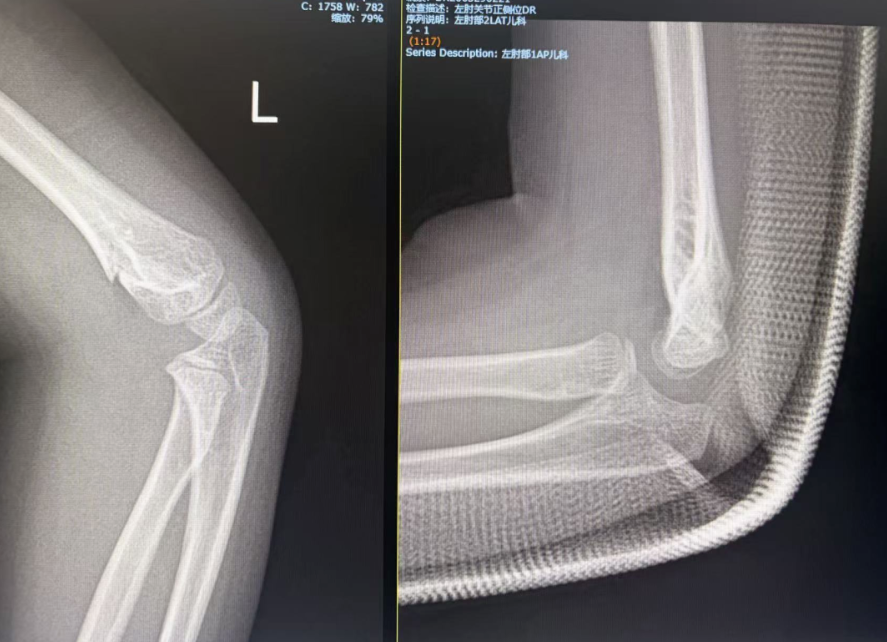

治疗案例①

5 岁女童(Gartland II 型):经过手法复位+石膏固定,四周复查时骨折已顺利愈合 。

5 岁 10 个月女童:同样采用石膏固定,第 33 天顺利拆除石膏,肘关节功能恢复良好 。